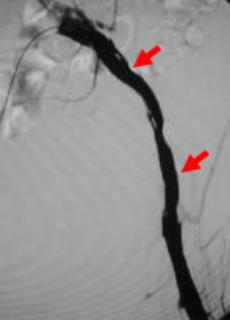

下肢动脉硬化闭塞症导致的右侧髂动脉闭塞,行走后右腿乏力,足部凉伴有疼痛破溃。造影提示右侧髂动脉重度狭窄,血流通过受限。

治疗前

介入治疗后,狭窄消失,血流通过顺利,下肢疼痛症状消失。

治疗后